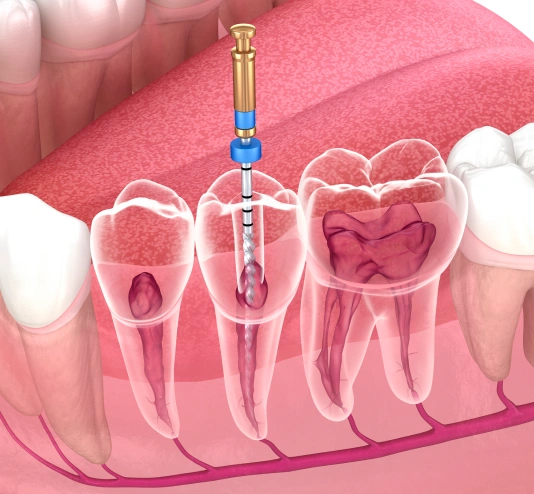

Save Your Tooth with a Root Canal

Endodontic treatment becomes necessary when the pulp (commonly referred to as the nerve of the tooth) becomes damaged from decay, a crack in the tooth, periodontal disease and even repeated dental procedures. Left untreated, the pulp inflammation or infection may cause pain or lead to an abscess. Root canal therapy involves removing the infected or inflamed pulp, thoroughly cleaning the tooth and sealing the canal space with a biocompatible filling. This therapy involves local anesthesia and may be completed in one visit. More complicated cases may require additional visits to our office. If your tooth is not amemable to endodontic treatment or if the chance of success is unfavorable, we will inform you at your consultation or when a complication becomes evident during or after treatment.